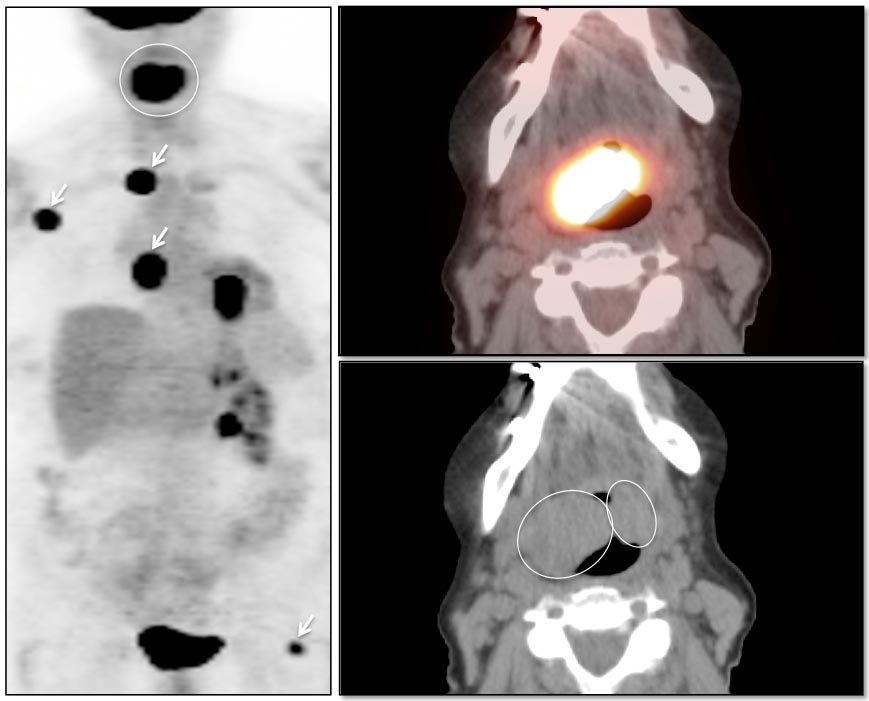

Palatine Tonsils

The palatine tonsils frequently demonstrate very intense metabolic activity.

Interpretation of tonsillar uptake is depends on the clinical presentation of the patient, the degree of FDG uptake, the size of the tonsils and the bilateral or unilateral nature of the findings.

- Bilateral and fairly symmetric FDG-uptake in non-enlarged palatine tonsils is almost always a normal finding.

- Bilateral and fairly symmetric FDG-uptake in enlarged palatine tonsils is nearly always inflammatory in nature (although can occasionally be seen with lymphoma).

- Unilateral or asymmetric increased FDG uptake within one palatine tonsil warrants careful and detailed assessment (addressed in detail, here).